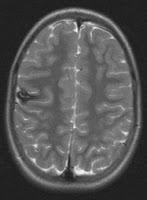

Los angiomas cavernosos (AC) son vasos

sanguíneos anormales localizados en el cerebro. Producen cefalea, trastornos

visuales, convulsiones y derrames cerebrales, tiene un componente genético,